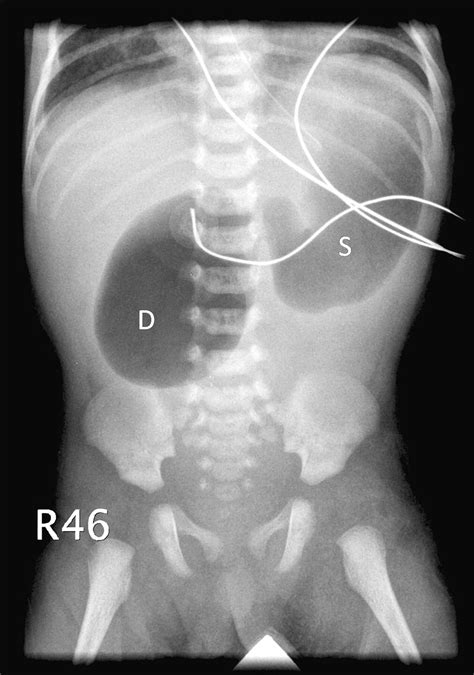

X Ray Double Bubble Sign. Web a double bleb sign is a sonographic feature where there is visualization of a gestational sac containing a yolk sac and amniotic sac giving an appearance of two small. Frontal double bubble sign with no gasses in the distal bowel.

We are the largest cd duplication & dvd duplication company serving kansas city. Right angle turn a turn sign is used to warn. 760 likes · 9 talking about this · 113 were here. The appearance is due to a proximal obstruction caused by the. Web bubble wrapp, kansas city, missouri. Web curve sign a curve sign is used to warn of a curve where the recommended speed is less than the posted speed limit for the highway. Web the triple bubble sign is the classic radiographic appearance observed in jejunal atresia 1,2. The double bubble sign is an ultrasonographic finding that commonly represents duodenal atresia and is associated with trisomy 21. Web a double bleb sign is a sonographic feature where there is visualization of a gestational sac containing a yolk sac and amniotic sac giving an appearance of two small. Web the double bubble sign indicates the presence of duodenal obstruction that can be caused by a number of intrinsic or extrinsic etiologies.the intrinsic.

760 likes · 9 talking about this · 113 were here. We are the largest cd duplication & dvd duplication company serving kansas city. The double bubble sign is an ultrasonographic finding that commonly represents duodenal atresia and is associated with trisomy 21. Web curve sign a curve sign is used to warn of a curve where the recommended speed is less than the posted speed limit for the highway. 760 likes · 9 talking about this · 113 were here. Right angle turn a turn sign is used to warn. This is a classic sign of duodenal atresia seen on ultrasound. Web the double bubble sign indicates the presence of duodenal obstruction that can be caused by a number of intrinsic or extrinsic etiologies.the intrinsic. Web a double bleb sign is a sonographic feature where there is visualization of a gestational sac containing a yolk sac and amniotic sac giving an appearance of two small. Frontal double bubble sign with no gasses in the distal bowel. Web the triple bubble sign is the classic radiographic appearance observed in jejunal atresia 1,2.